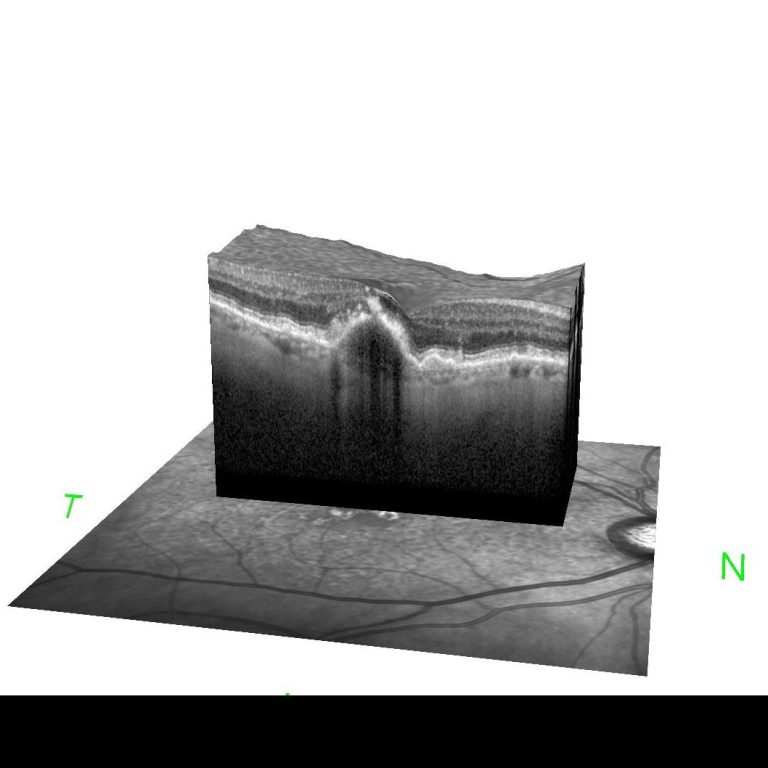

Die Stelle des schärsten Sehens der Netzhaut, die "Makula lutea", hier genauer die "Fovea centralis" dargestellt in unserer Praxis durch hochauflösende optische Cohärenztomographie (HR-OCT). Die Untersuchung ist völlig schmerzfrei und sekundenschnell angefertigt. Sie liefert ein sehr differenziertes Bild der einzelnen Netzhautschichten und des retinalen Pigmentepithels. Auch die Aderhaut kommt zur Abbildung. So können krankhafte Prozesse dieser extrem wichtigen Struktur sehr früh erkannt und behandelt werden.